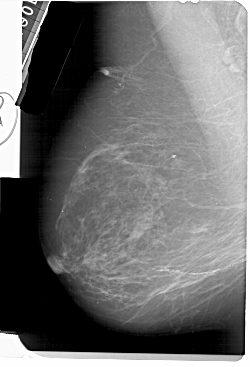

A_1511_1.LEFT_MLO

LEFT_MLO LINES 5491 PIXELS_PER_LINE 3736 BITS_PER_PIXEL 12 RESOLUTION 43.5 NON_OVERLAY